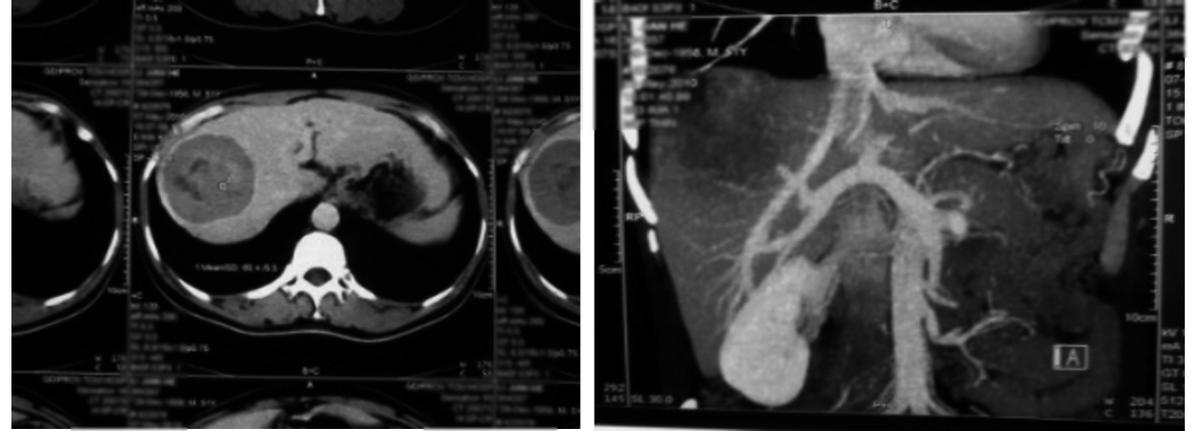

直到后来上述症状逐渐加重,刘明才意识到事情可能并不简单,6月,刘明在县医院进行检查,AFP:5420ng/mL,行腹部B超示:右肝后叶实质性占位,考虑肝癌。后来在儿子的陪同下到市中心医院进行更进一步的检查,行CT检查示右肝后叶结节占位病变,约7.6cm×7.5cm×8.5cm,增强扫描见强化,考虑原发性肝癌。

由于其肝癌已经到了晚期,医生建议行肝动脉DSA+灌注+栓塞术(术中化疗用药:雷替曲塞、奥沙利铂、重组人血管内皮抑制素)。然而第一次治疗后,刘明的副反应非常剧烈,胃脘部胀痛、反酸烧心、食欲不振、肝区疼痛等,让他不愿意继续治疗。